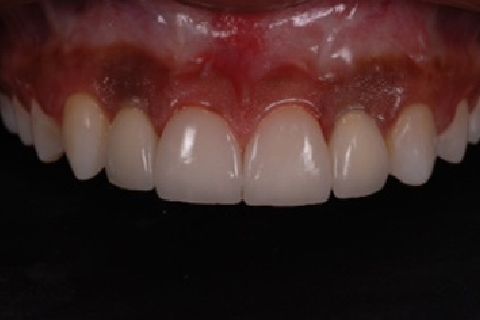

''Neste caso, a paciente gostaria de melhorar a estética do seu sorriso, prejudicada pela agenesia de ambos os incisivos laterais superiores. Devido à baixa disponibilidade óssea, observada na tomografia computadorizada, optou-se pela instalação de implantes estreitos (Xive – Dentsply Implants – 3.0 mm de diâmetro) com regeneração simultânea (Biooss e Biogide – Geistlich), ao invés de realizar enxerto ósseo prévio. Após osseointegração, foi realizado condicionamento gengival com provisórios e novo enceramento diagnóstico. O caso foi finalizado com coroas livres de metal sobre os implantes e microlaminados cerâmicos sobre os incisivos centrais (e.max - dissilicato de lítio – Ivoclar Vivadent), visando o mínimo desgaste de estrutura dental sadia. ''